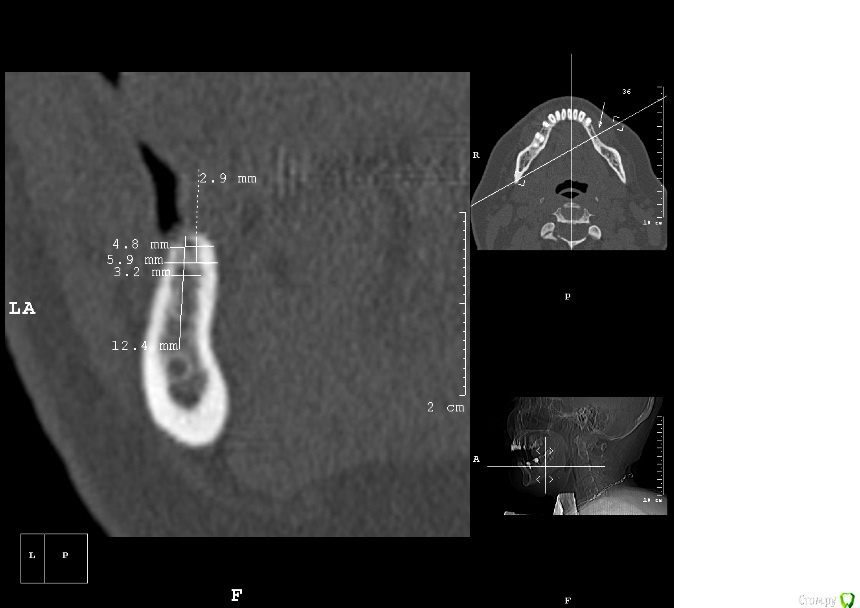

kamranchick Опубликовано 25 апреля, 2016 Поделиться Опубликовано 25 апреля, 2016 Пациентка обратилась с целью восстановления жевательного отдела.финансовый вопрос не интересует, хотелось бы чтобы с минимальными рисками.1.я думаю - удаление, 3 винта, сосидж, 5 пинов.чтобы вы предложили? Ссылка на комментарий

kamranchick Опубликовано 2 мая, 2016 Автор Поделиться Опубликовано 2 мая, 2016 ну я указал 3 сегмент, 3 винта, следовательно удаление 5 го зуба, установка имплантатов в область 35 36 и 37 Ссылка на комментарий

dantist_movani Опубликовано 2 мая, 2016 Поделиться Опубликовано 2 мая, 2016 Спасибо, ответы давно уже получил, и дело не в срезах вовсе, чем вам срезы не угодили?на срезах указаны позиции 3.5,3.6,3.7,3.8? В какие позиции "3 винта" и что удалить, я просто может не понял? Ссылка на комментарий